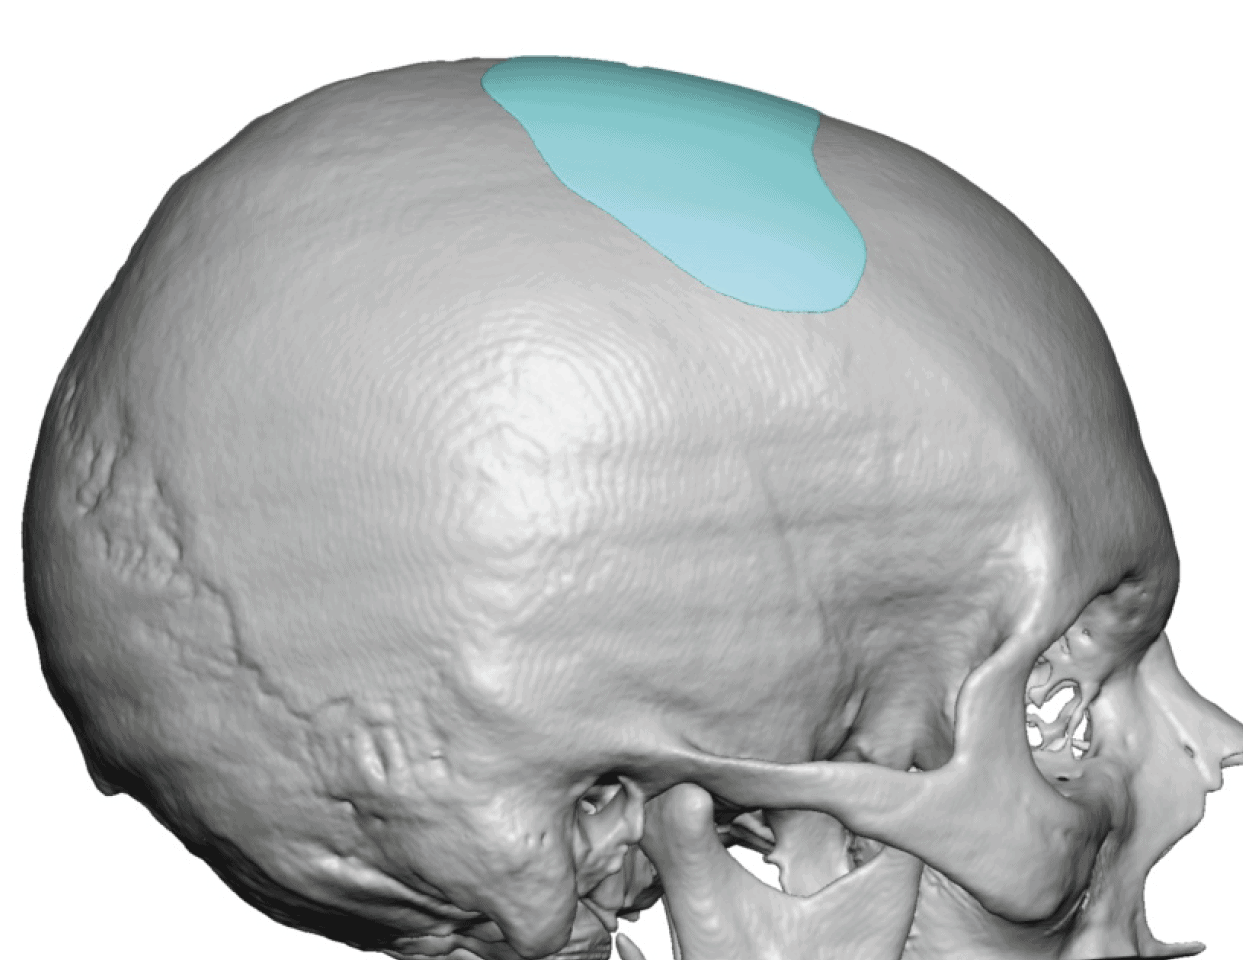

Patient 49

Desire for further skull augmentation after a primary skull implant.

Five years after an initial custom skull implant placement a new custom skull implant that increased the volume by 35% was placed.

Desire for further skull augmentation after a primary skull implant.

Five years after an initial custom skull implant placement a new custom skull implant that increased the volume by 35% was placed.